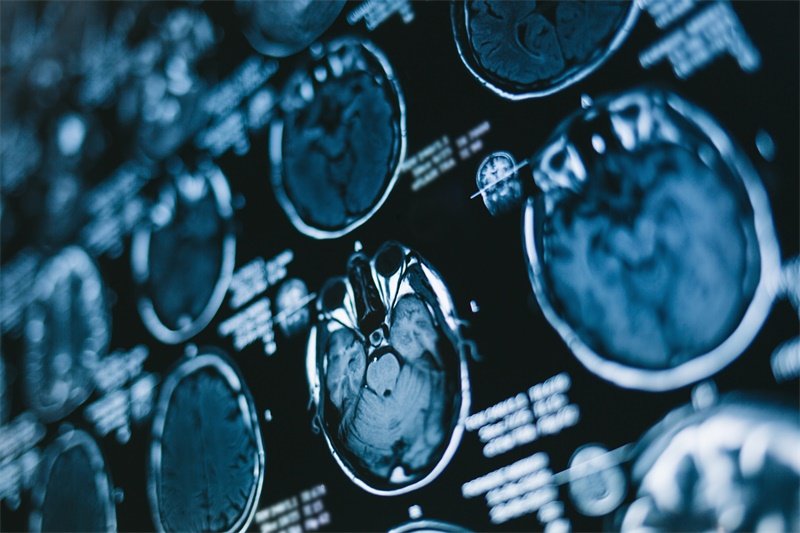

对于可能存在的囊样占位病灶,及时诊断是至关重要的。影像学检查,如CT(计算机断层扫描)和MRI(核磁共振成像),通常是初步筛查的关键手段。

CT扫描可以有效识别囊肿的存在及其大小,同时帮助医生评估周围脑组织的状态。而MRI则在显示囊肿内部结构方面更具优势,能够提供更为详尽的解剖信息。